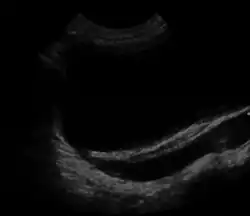

| Ultrasound image showing abnormal vesicoureteral junction and dilated distal ureter resulting in primary vesicoureteral reflux (VUR). | |

- Abdominal ultrasound

An abdominal ultrasound might suggest the presence of VUR if ureteral dilatation is present; however, in many circumstances of VUR of low to moderate, even high severity, the sonogram may be completely normal, thus providing insufficient utility as a single diagnostic test in the evaluation of children suspected of having VUR, such as those presenting with prenatal hydronephrosis or urinary tract infection (UTI).[4]